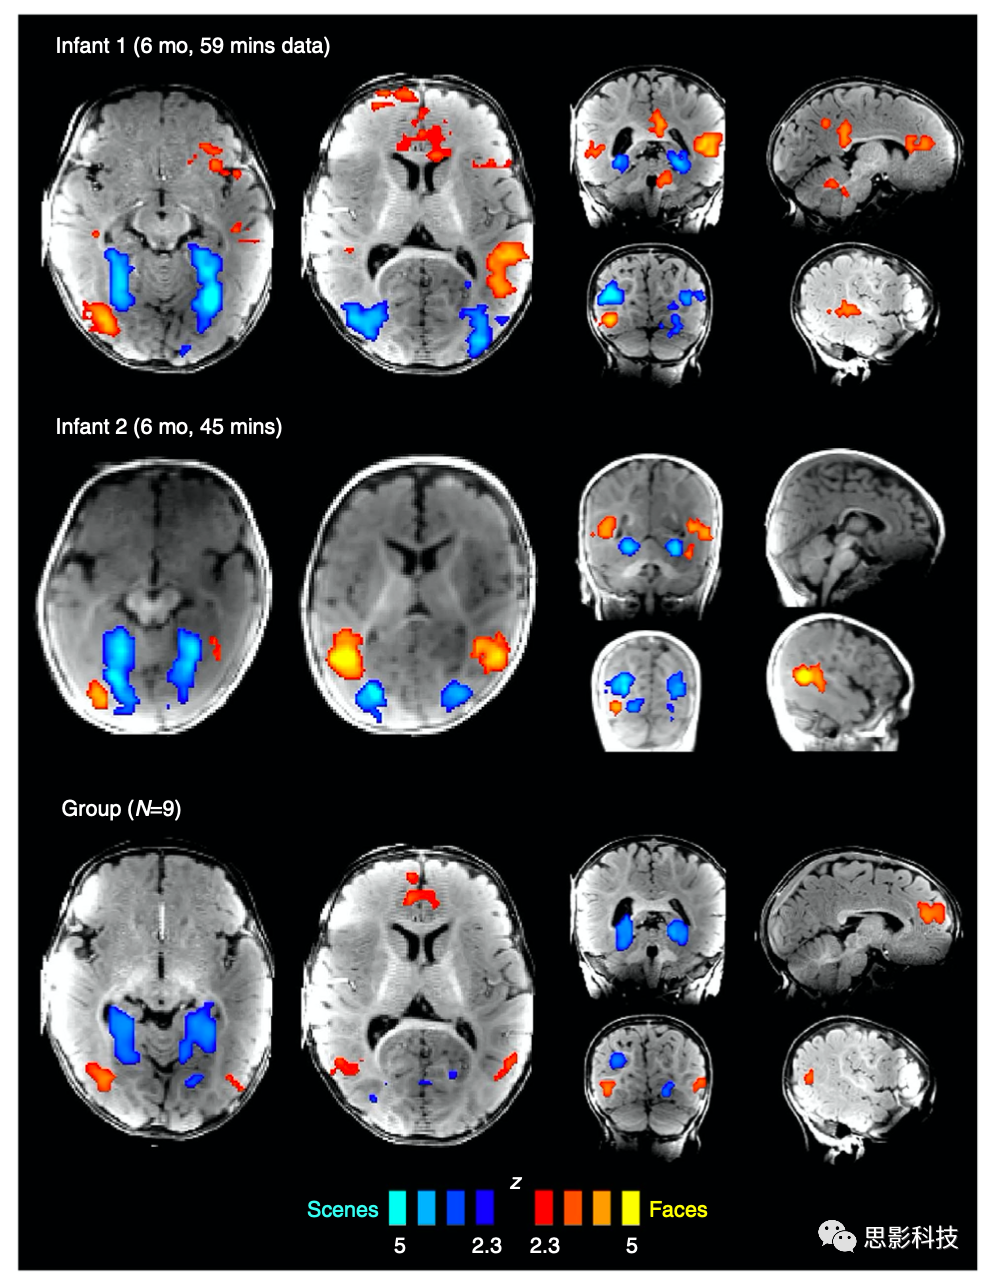

3、Nature Communications:婴幼儿高级视觉皮层结构

人类心智和大脑的结构有多少在出生时就已经确定,又有多少是由经验产生的?针对此问题,麻省理工和剑桥大学的Ben Deen等人在Nature Communications杂志上发文,考虑了纹外视皮层的测试案例,这是一个高度系统的功能组织,几乎存在于每一个正常的成年人中,包括那些偏好行为显著的刺激类别的区域,如面孔、身体和场景。他们开发了一种新的方法,用功能磁共振成像(fMRI)扫描清醒婴儿,同时让婴儿观看多种视觉刺激。结果报告表明,4-6个月大婴儿的视觉皮层包含对抽象类别(面部和场景)有优先反应的区域,其空间组织类似于成年人。但是,婴儿和成人之间,跨多个视觉类别的精确反应曲线和活动模式有所不同。这些结果表明,视觉皮层中类别偏好的大规模组织在出生后的几个月内是和成年人类似的,但随后通过发育得以细化完善。